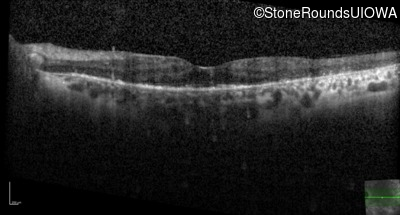

Age at visit: 55 years

Age at visit: 57 years